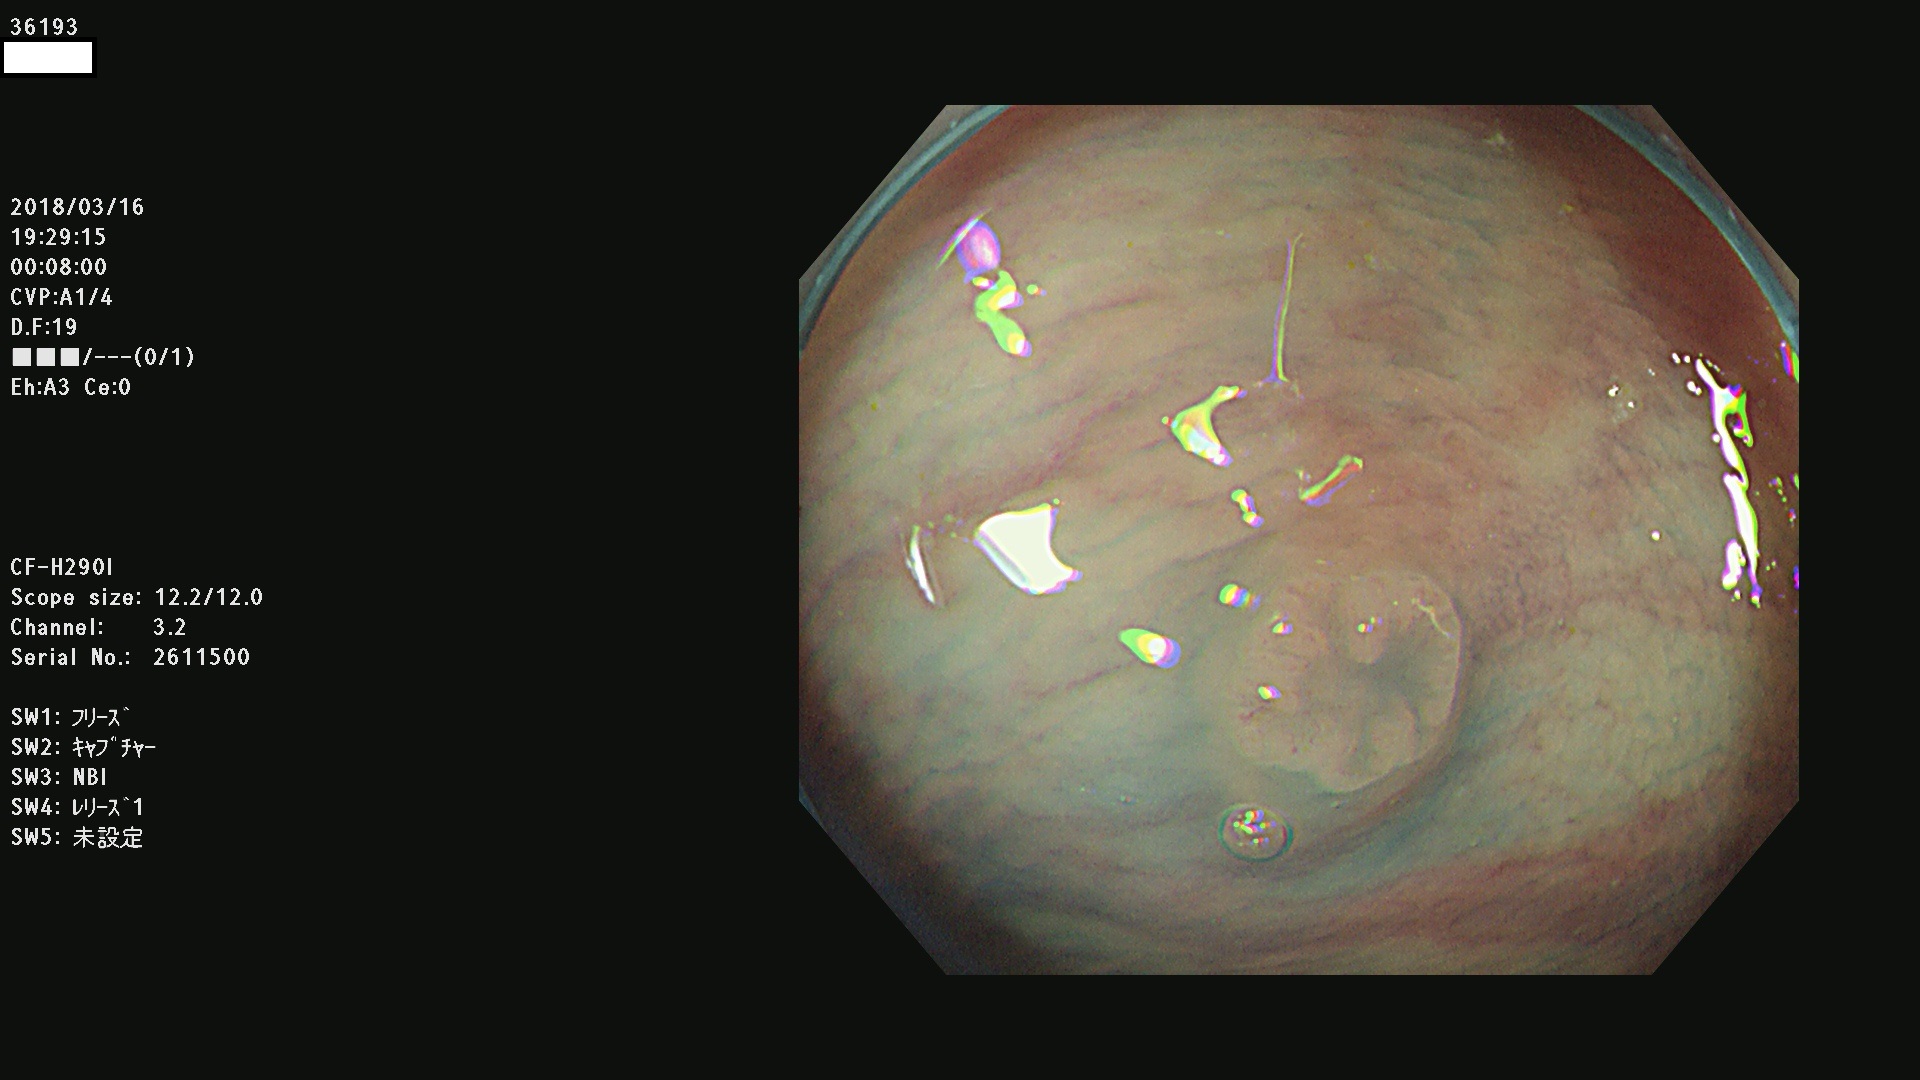

発見困難で危険性の高い平坦型病変(上記100名より抽出) ![]()